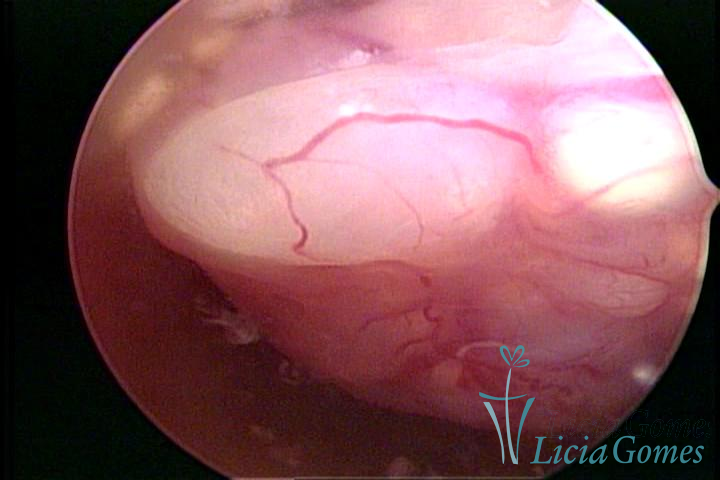

Este pode apresentar uma gama variável de aspectos macroscópicos, com aspecto pseudopolipoide; lembrando tecido cerebroide ou com reação deciduoide;a vascularização superficial é mais evidente e com vasos em formatos de saca-rolha ou espirais visualizando também a vascularização com atípias, com aumento do calibre dos vasos superficiais, pode ser encontrado também tecido em necrose, poderá haver um pequenos dendritos (papilomatoso).